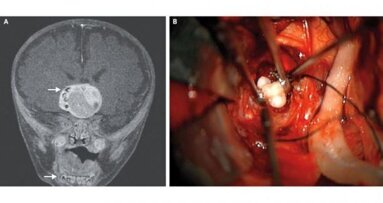

MARYLAND, VS – Bij een vier maanden oude Amerikaanse baby is een hersentumor met tanden verwijderd. De baby had een zeer zeldzame, langzaam groeiende...